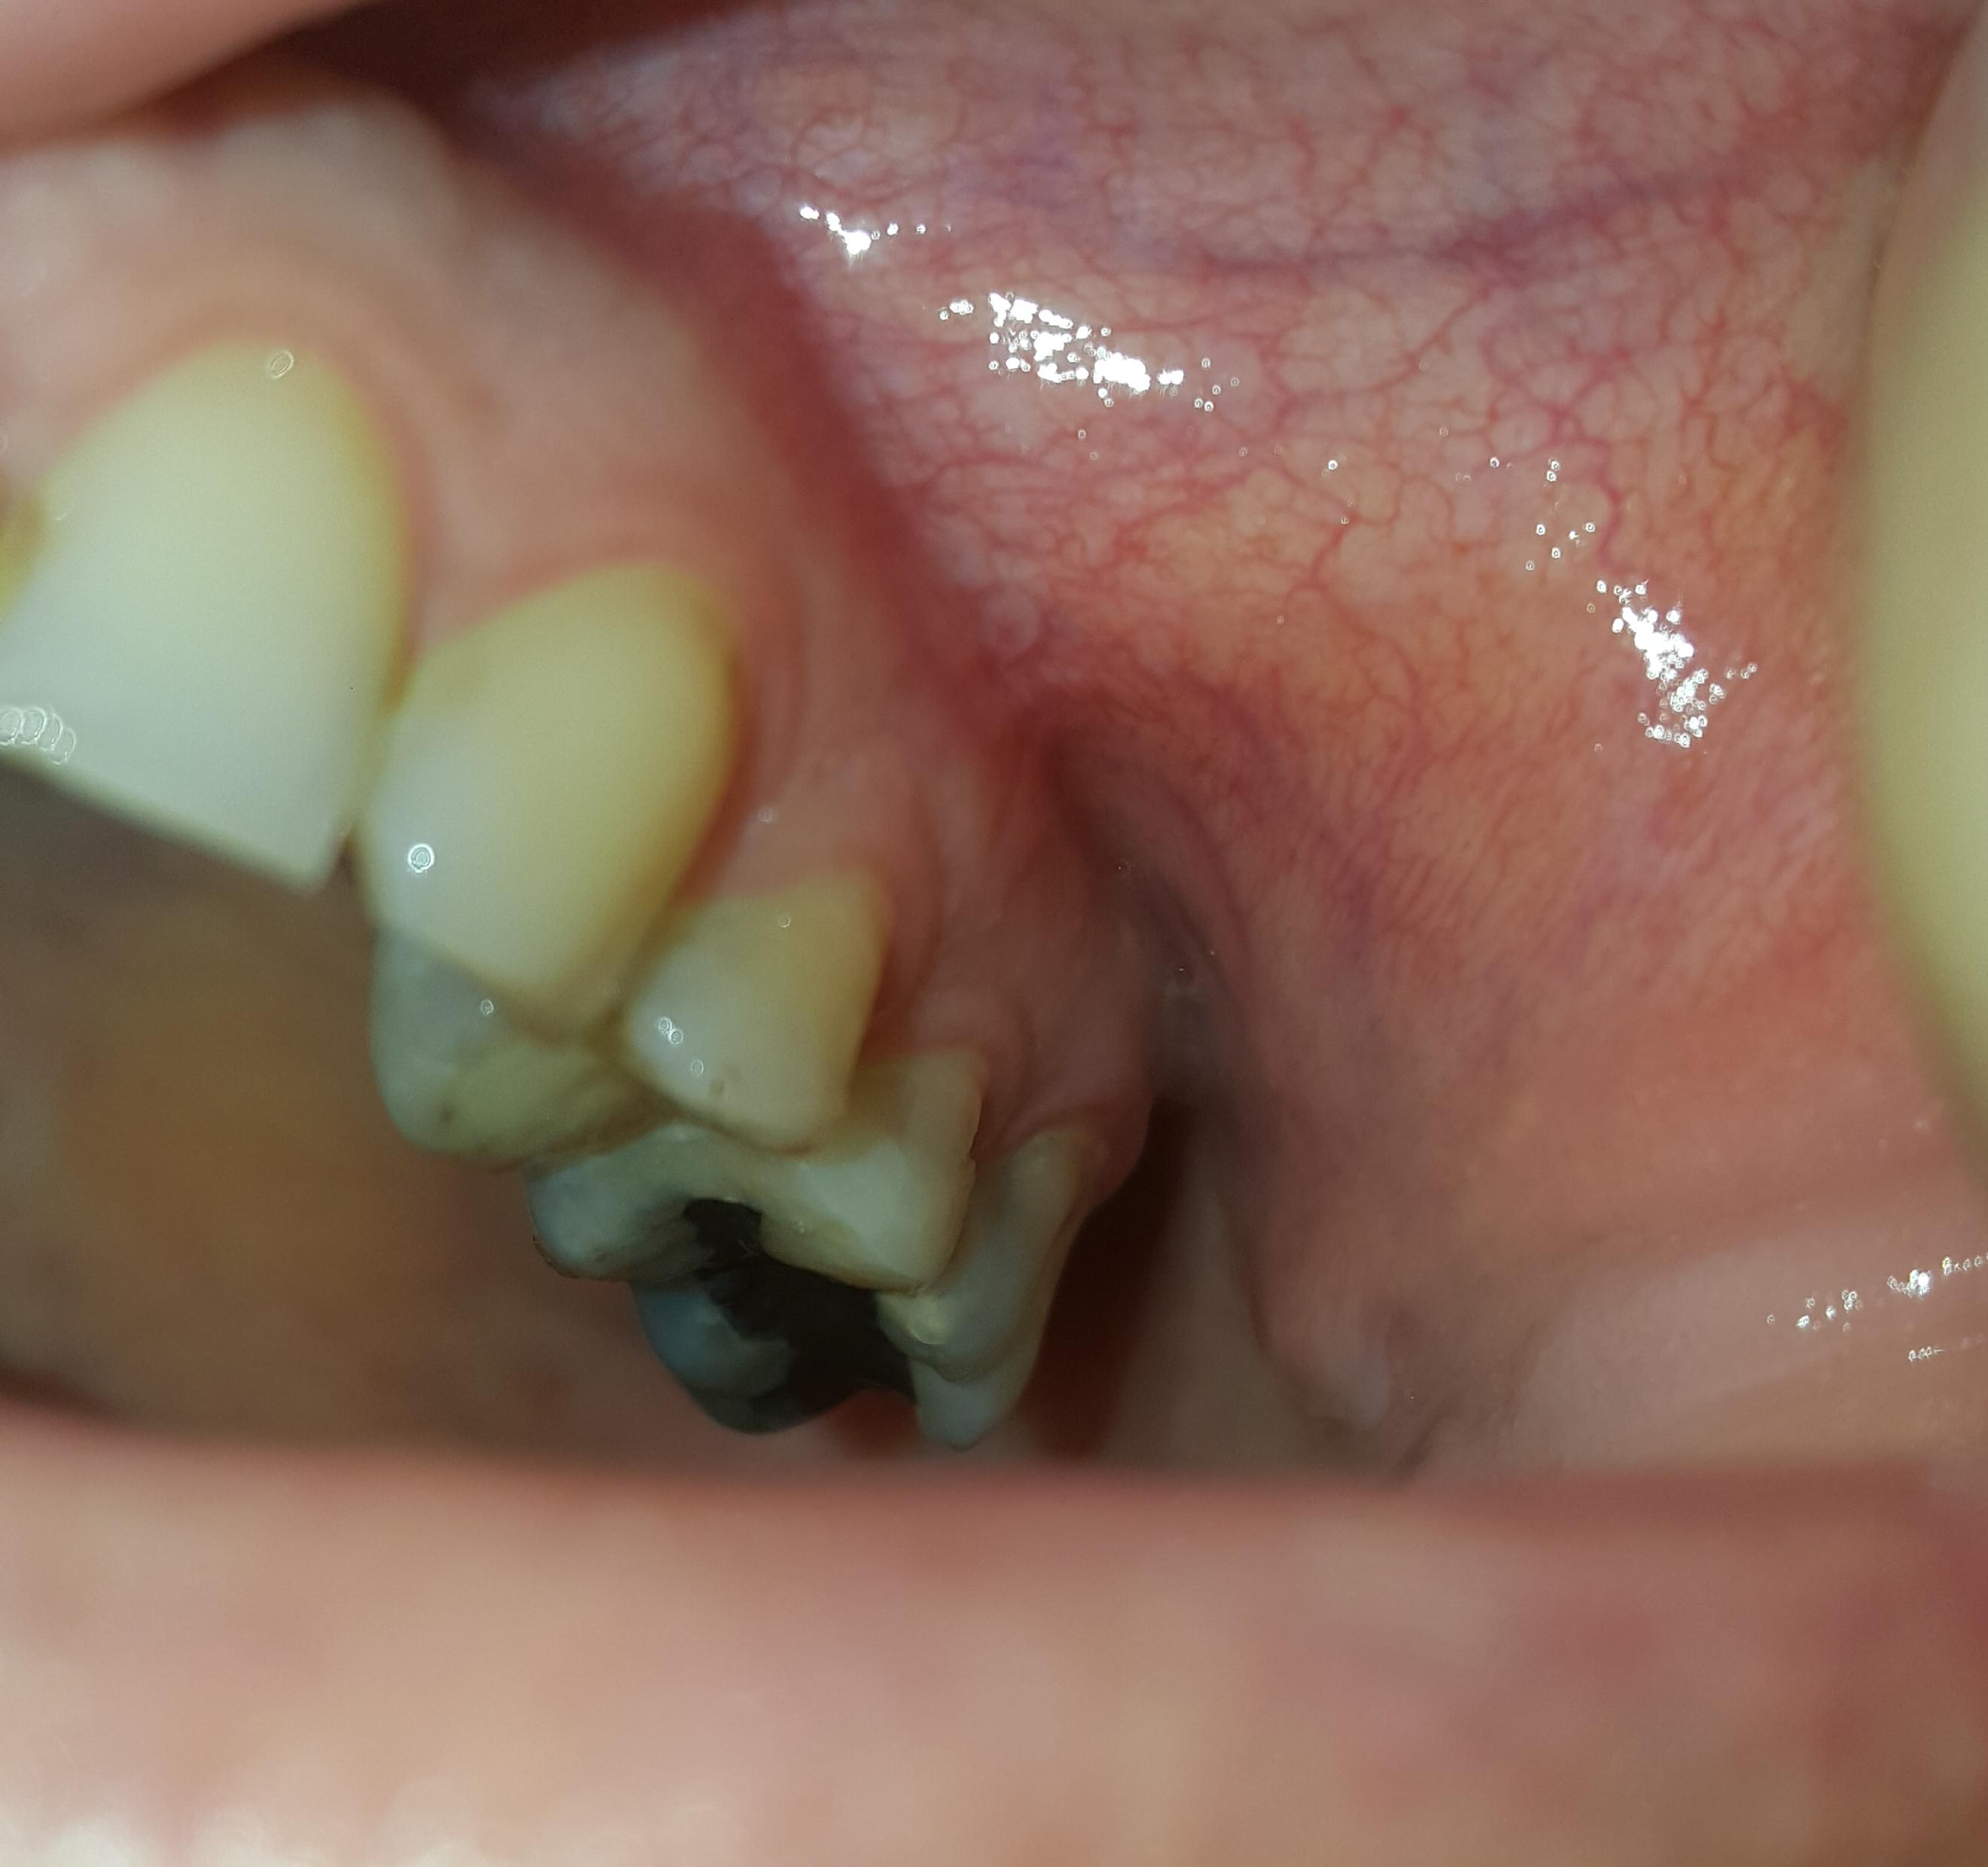

Zie bultje in de mond. Is dit een fistel?

Foto 1 is van vandaag, Foto 2 van gisteren.